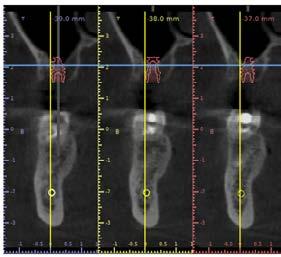

40 años acudió para la rehabilitación del sector posterior superior, pues presentaba un defecto vertical en el cuadrante superior derecho a la altura del primer molar, una altura óseorresidual de 3.5 mm y un tipo óseo III. Dadas las condiciones, se optó por la técnica de oseodensificación para la elevación del piso del seno maxilar y la preparación del lecho implantario. Entre los hallazgos descritos en los resultados se encontró una elevación sinusal de al menos 6 mm, evidenciada en las imágenes radiográficas intraoperartorias, que permitió la colocación de un implante de 5 mm de plataforma por 8 mm de longitud, ubicado 1 mm en posición subcrestal. Una tomografía

axial computarizada confirmó la situación del implante, así como la efectividad de la oseodensificación y la elevación del piso sinusal de 6 mm. la osteointegración del implante se completó sin necesidad de procedimientos quirúrgicos adicionales de mayor complejidad. Se concluye que la oseodensificación es una técnica eficaz y predecible para la osteotomía y la elevación sinusal transcrestal, favorece la estabilidad primaria del implante y constituye un procedimiento mínimamente invasivo.

Figura 2. Planeación en tomografía axial computarizada: a) vista sagital, b) vista transversal, c) vista 360°, d) reconstrucción 3D y e) ortopantomografía.

Planeación tomográfica

Se creó un mapeo óseo para evaluar las dimensiones de altura y anchura ósea disponibles para la colocación del implante dental y su posterior restauración protésica. El análisis reveló una cantidad reducida de tejido óseo en el piso del seno maxilar (3.61 mm), lo que condicionó la planificación del procedimiento. Para la rehabilitación implantológica, se requiere la colocación de un

implante de al menos 8 mm de altura por 5 mm de diámetro, con adecuado espacio vestíbulo-palatino e interoclusal. No obstante, luego de considerar la insuficiencia de volumen óseo en sentido vertical y el grado de neumatización del seno maxilar, se determinó que la colocación del implante mediante técnicas convencionales no era viable, por ello la necesidad de procedimientos de aumento óseo para lograr una rehabilitación adecuada (Figura 2).